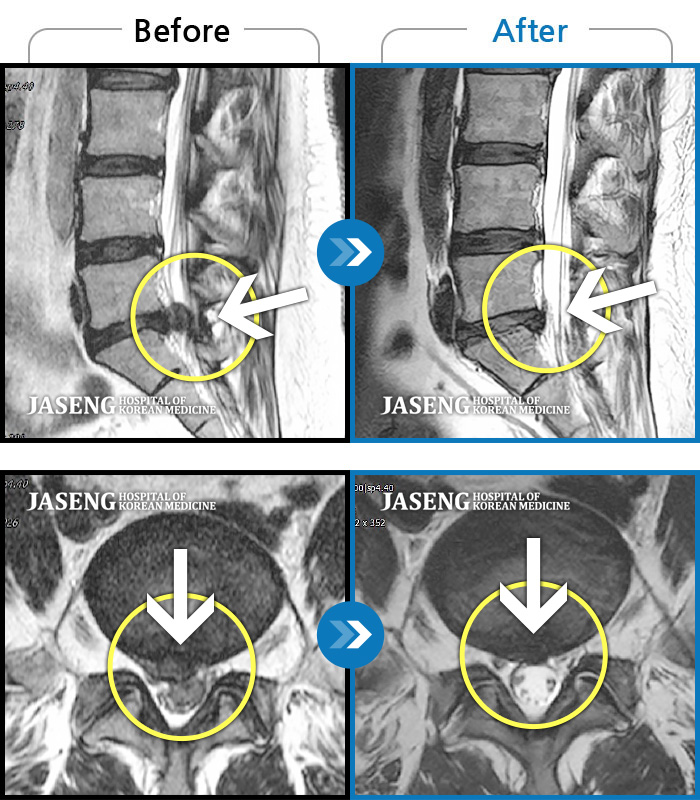

허리디스크

강남 · 강만호 원장

허리통증 및 왼쪽 다리 통증으로 운전이 불가능했습니다.

촬영시기

2023.10.16 ~ 2024.10.14

2024.10.23

조회수 457